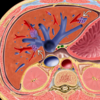

Budd-Chiari.

Achados característicos:

Hipertrofia do lobo caudado; atrofia / necrose do parênquima periférico – realce em mosaico; veias colaterais intra-hepáticas; nódulos regenerativos; ascite.

Obstrução da drenagem venosa (veias centro-lobulares, veias hepáticas e VCI), levando a um estado de hipercoagubilidade.

1. Hipertrofia do lobo caudado;

2. Atrofia / necrose do parênquima periférico – realce em mosaico;

3. Veias colaterais intra-hepáticas;

4. Nódulos regenerativos;

5. Ausência de fluxo na VCI;

6. Ascite.